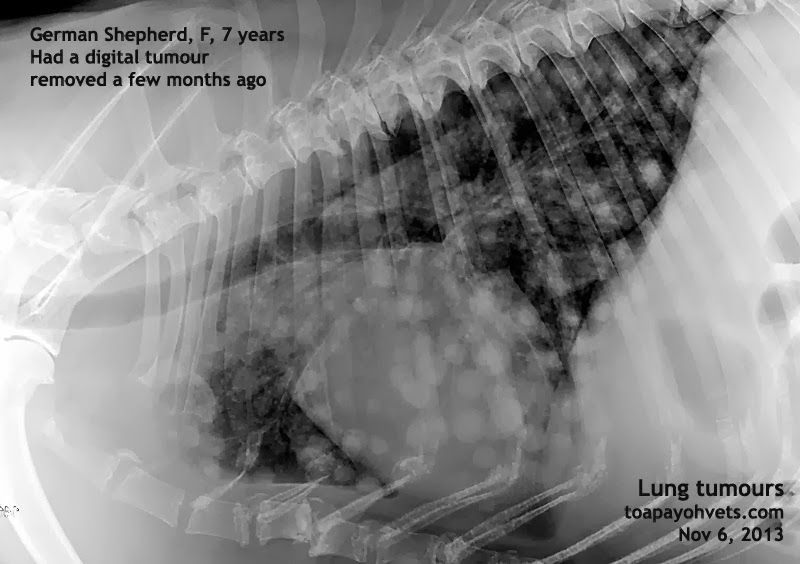

From 2010vets.blogspot.com

Veterinary, Photography and Travel Stories for vet students and pet Lung Issues In Older Dogs If your old dog’s breathing gradually gets worse and worse, don’t assume it’s okay, and don’t assume nothing can be done. — older dog breathing heavily—with older dogs, underlying medical conditions are more likely such as heart. — dyspnea, or troubled breathing, and tachypnea, or rapid breathing, panting or coughing can all be signs of serious underlying. However,. Lung Issues In Older Dogs.